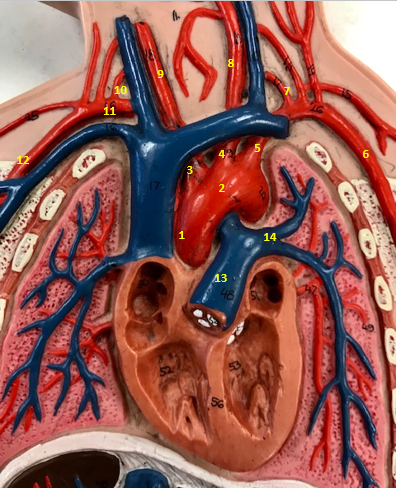

Aorta

Name #2

Brings blood out of left ventricle

Function of aorta

Brachiocephalic artery

Name #3

Supplies oxygenated blood to right arm shoulder neck and head

Function of brachiocephalic artery

Left common carotid artery

Name #4

Supplies oxygenated blood to left neck and head

Function of left common carotid artery

Left subclavian artery

Name #5

Supplies oxygenated blood to left arm shoulder

Function of left subclavian artery

Left axillery artery

Name #6

supplies blood to left armpit and upper limb

Function left axillary artery (6)

Left vertebral artery

Name #7

Supplies blood to brain and spinal cord

Function of left vertebral artery (7)

Left common carotid artery

Name #8

Supplies blood to left neck and head

Function of left common carotid artery (8)

Right common carotid artery

Name #9

Supplies oxygenated blood to right neck and head

Function of right common carotid artery (9)

Right vertebral artery

Name #10

Supplies blood to brain and spinal cord

Function of right vertebral artery (10)

Right subclavian artery

Name #11

Supplies blood to right arm and shoulder

Function of right subclavian artery

Right axillery artery

Name #12

Supplies blood to right armpit and upper limb

Function of right axillery artery (12)

Pulmonary trunk

Name #13

Bring blood out of right ventricle to lungs

Function of pulmonary trunk (13)

Left pulmonary artery

Name #14

Bring blood to left lung

Function of left pulmonary artery (14)